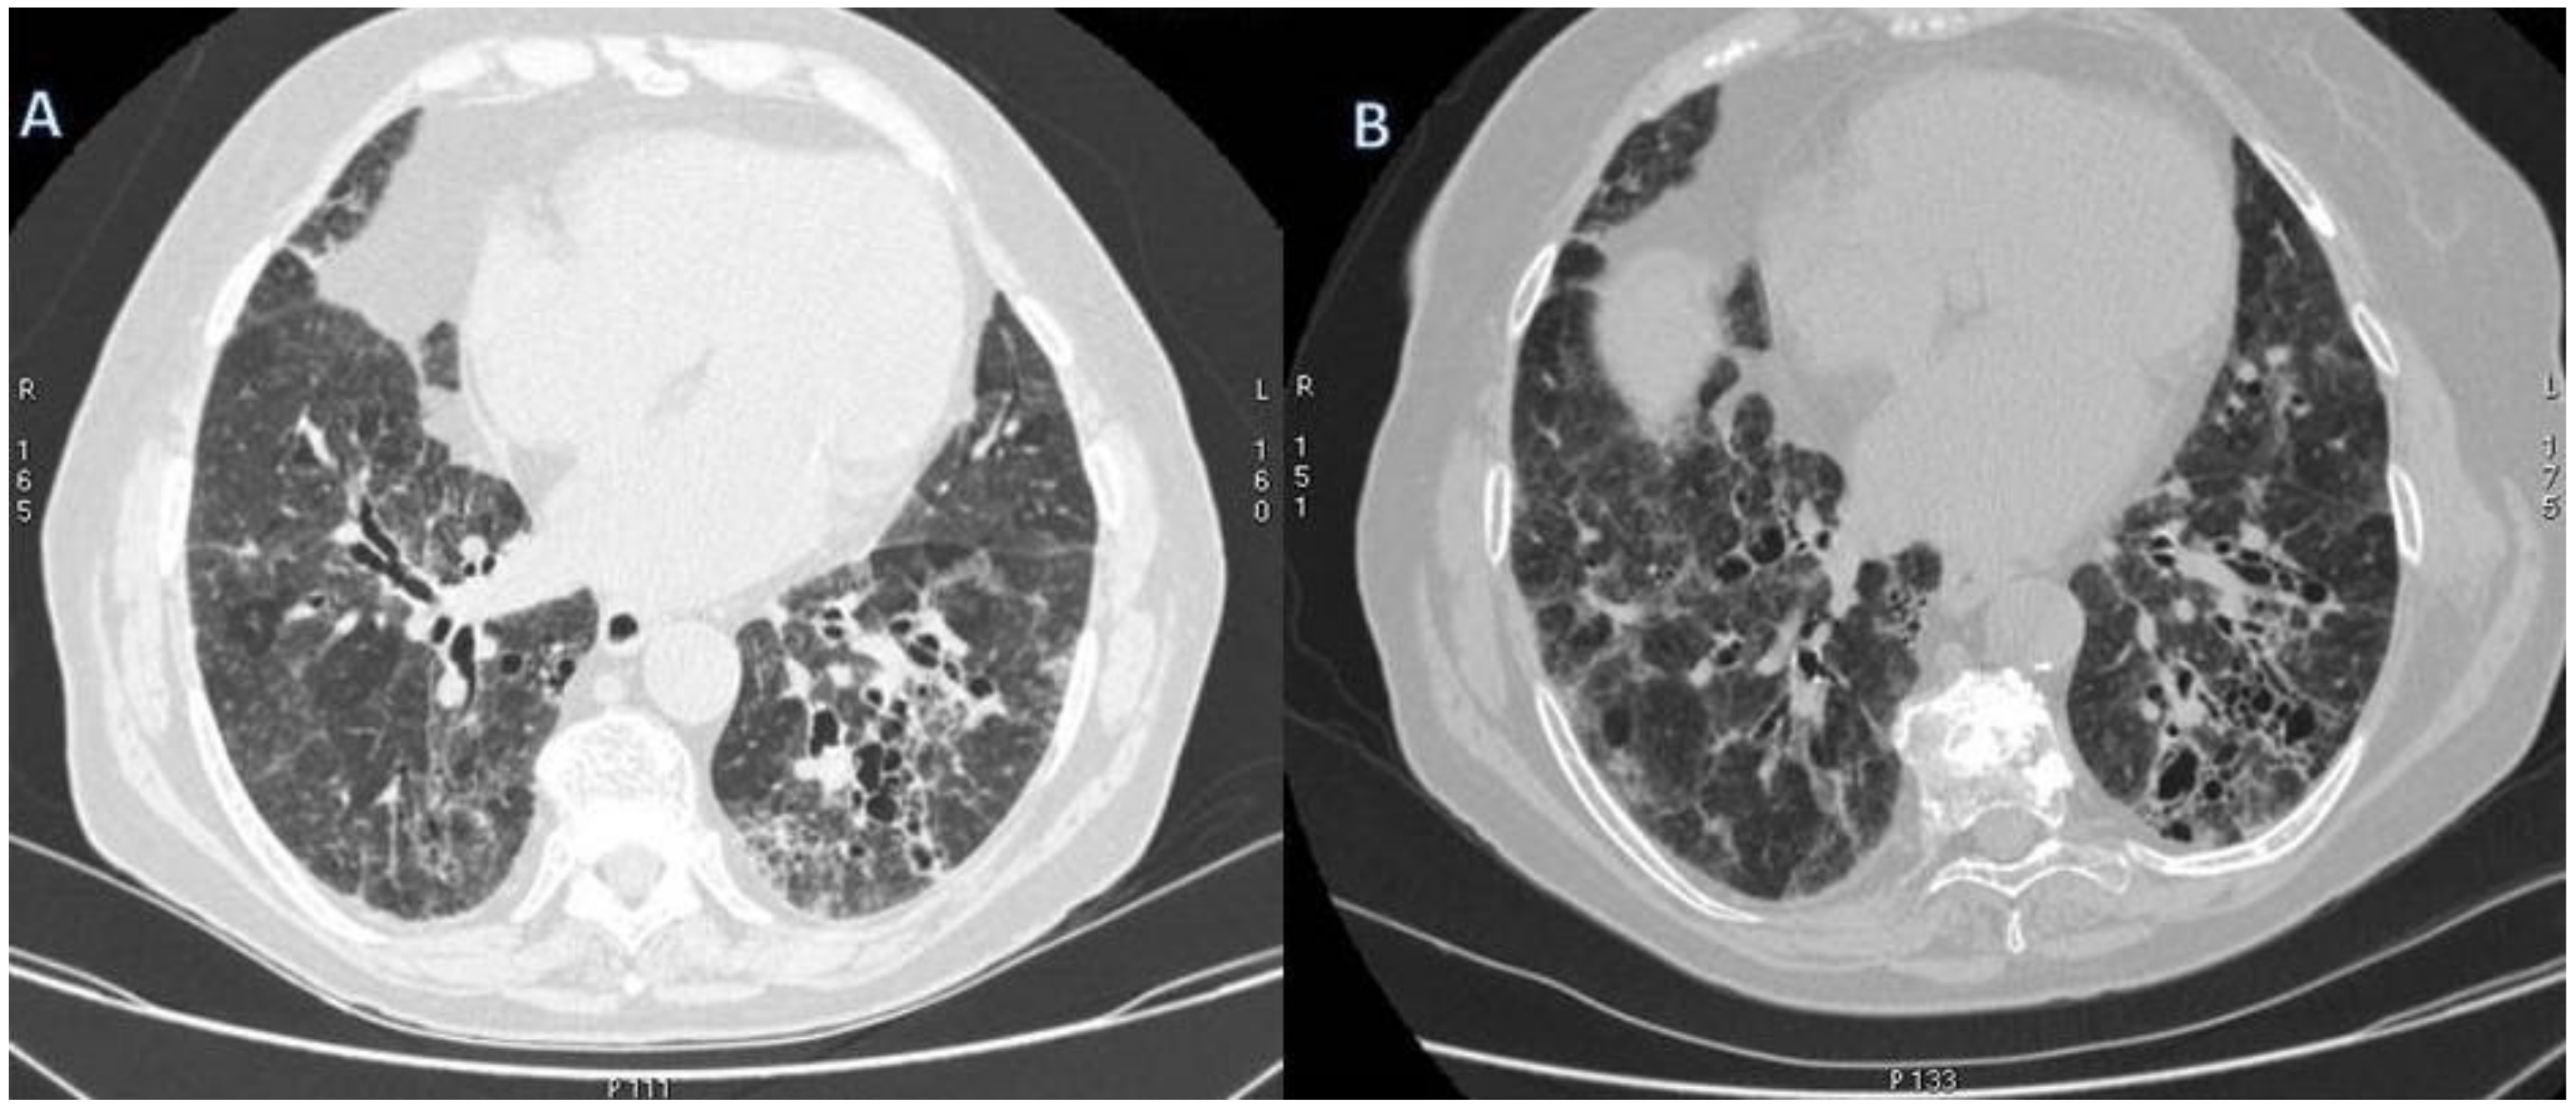

2.4. Granulomatosis with Polyangiitis (GPA-Wegener’s Disease)

| GPA | Solid nodules, GGOs due to hemorrhagic alveolitis (common); halo sign, crazy paving (less common) |